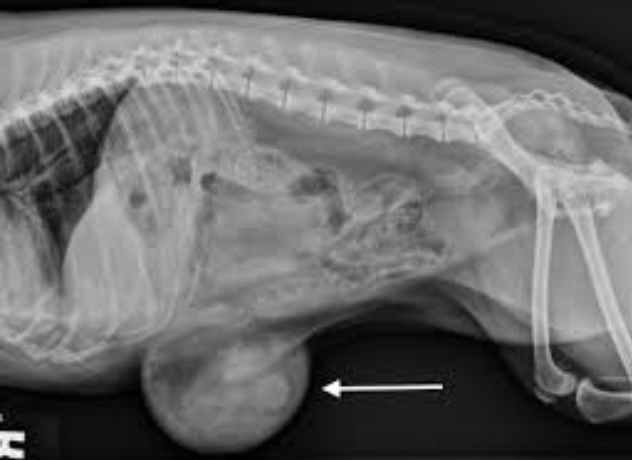

亲戚家的马里努阿犬来诊所时,主人向我们诉说犬4月龄,腹下部一直有一个球状物体。触感时大时小,手感柔软。以往并没有红、热、肿、痛的反应。该犬精神状态较好,刚开始主人并没有重视,但过了一段时间,发现其腹部球状物越来越大,主人深知不妥赶紧就医。

临床检查后发现该犬的脐部有椭圆形肿胀物,长5cm,宽3cm,按压无疼痛排斥反应。其肿胀物可纳腹腔,摸其腹壁还可感知有环状轮廓。根据临床症状和触诊结果,综合分析得出该犬为典型脐疝。

因疝气存在于腹内,兽医可能会建议患犬进行X光检查以评估患犬的状况。如若确定以手术为修复脐疝的手段后,兽医会让患犬进行麻醉测试,确保患犬能够接受麻醉程序。

根据主人主诉患犬情况,再结合X光结果确定腹部任何组织后,可确诊为脐疝。